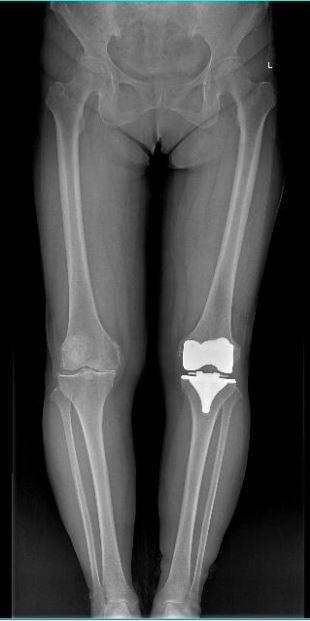

女 65岁

左侧膝关节置换术后

左侧膝关节置换术后复查

通过全景拼接图像可以清晰显示双下肢对比情况,为术后评估提供更多影像学资料。